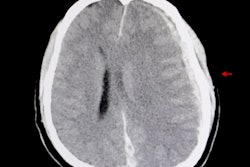

An artificial intelligence (AI) algorithm was able to accurately identify acute intracranial hemorrhage (ICH) on head CT scans and even find some tiny hemorrhages that could be overlooked by radiologists, according to research published online October 21 in the Proceedings of the National Academy of Sciences.

A research team from the University of California, San Francisco (UCSF) and the University of California, Berkeley (UC Berkeley) developed a deep-learning model that can detect and localize an ICH -- and classify its subtype -- on a head CT exam in one second. In testing, the model performed better than two of the four expert radiologists involved in the study.

The algorithm's performance was compared with that of four expert radiologists on a separate test set of 200 head CT exams, including 25 positive and 175 negative cases. The algorithm yielded an area under the curve (AUC) of 0.991 ± 0.006, and it identified some small abnormalities that were missed by radiologists. Importantly, these results were achieved with an acceptable level of false positives, according to the researchers.

"Algorithm performance exceeded that of 2 of 4 American Board of Radiology (ABR)-certified radiologists with attending-level experience ranging from 4 to 16 [years]," the authors wrote. "In addition, PatchFCN achieved 100% sensitivity at specificity levels approaching 90%, making this a suitable screening tool for radiologists based on an acceptably low proportion of false positives."